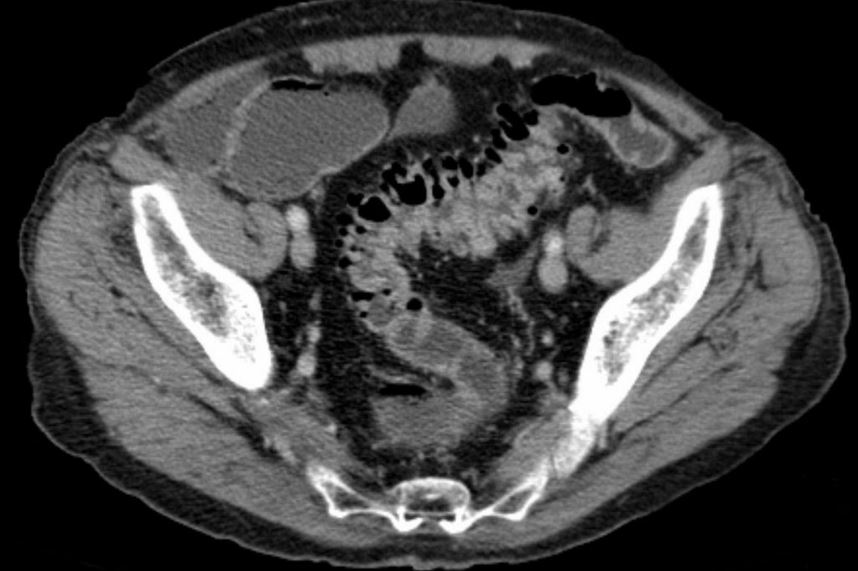

Let’s stop using antibiotics for uncomplicated diverticulitis

Guest posting : Dr Daniel Isacson, local GP (ex Swedish researcher) The evidence is out and there is no proven benefit in recovery or complication rates in treating these patients with or without antibiotics, but still many GPs and surgeons prefer to use antibiotics. How do we get the word across?